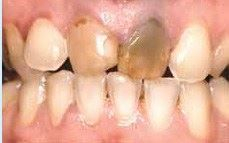

Før: De midterste fortænder trænger til to kroner.

Efter

Metalkeramikkroner består af en skal af guld, hvorpå der brændes et lag af tandfarvet porcelæn. De kan anvendes på næsten alle tænder. Ved meget lyse og gennemskinnelige fortænder er porcelænskroner dog at foretrække.